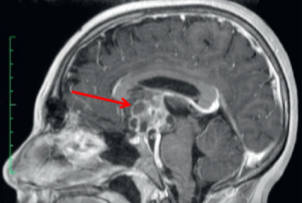

craniopharyngioma

slow growting benign tumors in suprasellar region

arise from remnants of Rathke’s pouch

benign, but locally aggressive

solid + cystic w/ calcification

erosion of dorsum sella

spreading of anterior & posterior clinoids